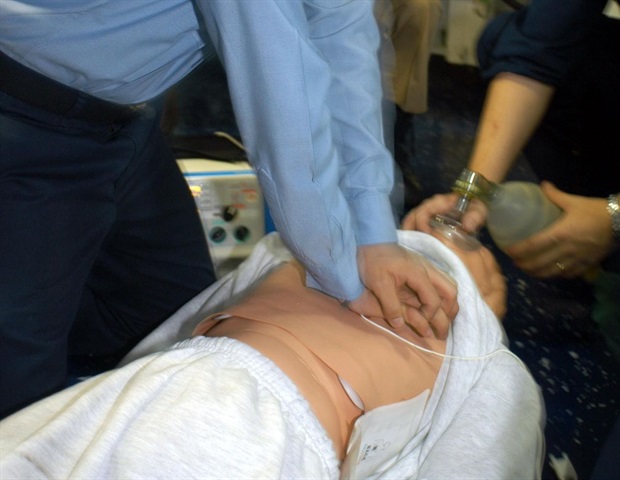

מחקר מזהה תאי חיסון מרכזיים שיכולים להגן על המוח לאחר דום לב

למרות שיפורים בהחייאה ושיעורי הגעת החולים לבית החולים, רק כ-10% מהאנשים שורדים בסופו של דבר לאחר דום לב מחוץ לבית

למרות שיפורים בהחייאה ושיעורי הגעת החולים לבית החולים, רק כ-10% מהאנשים שורדים בסופו של דבר לאחר דום לב מחוץ לבית